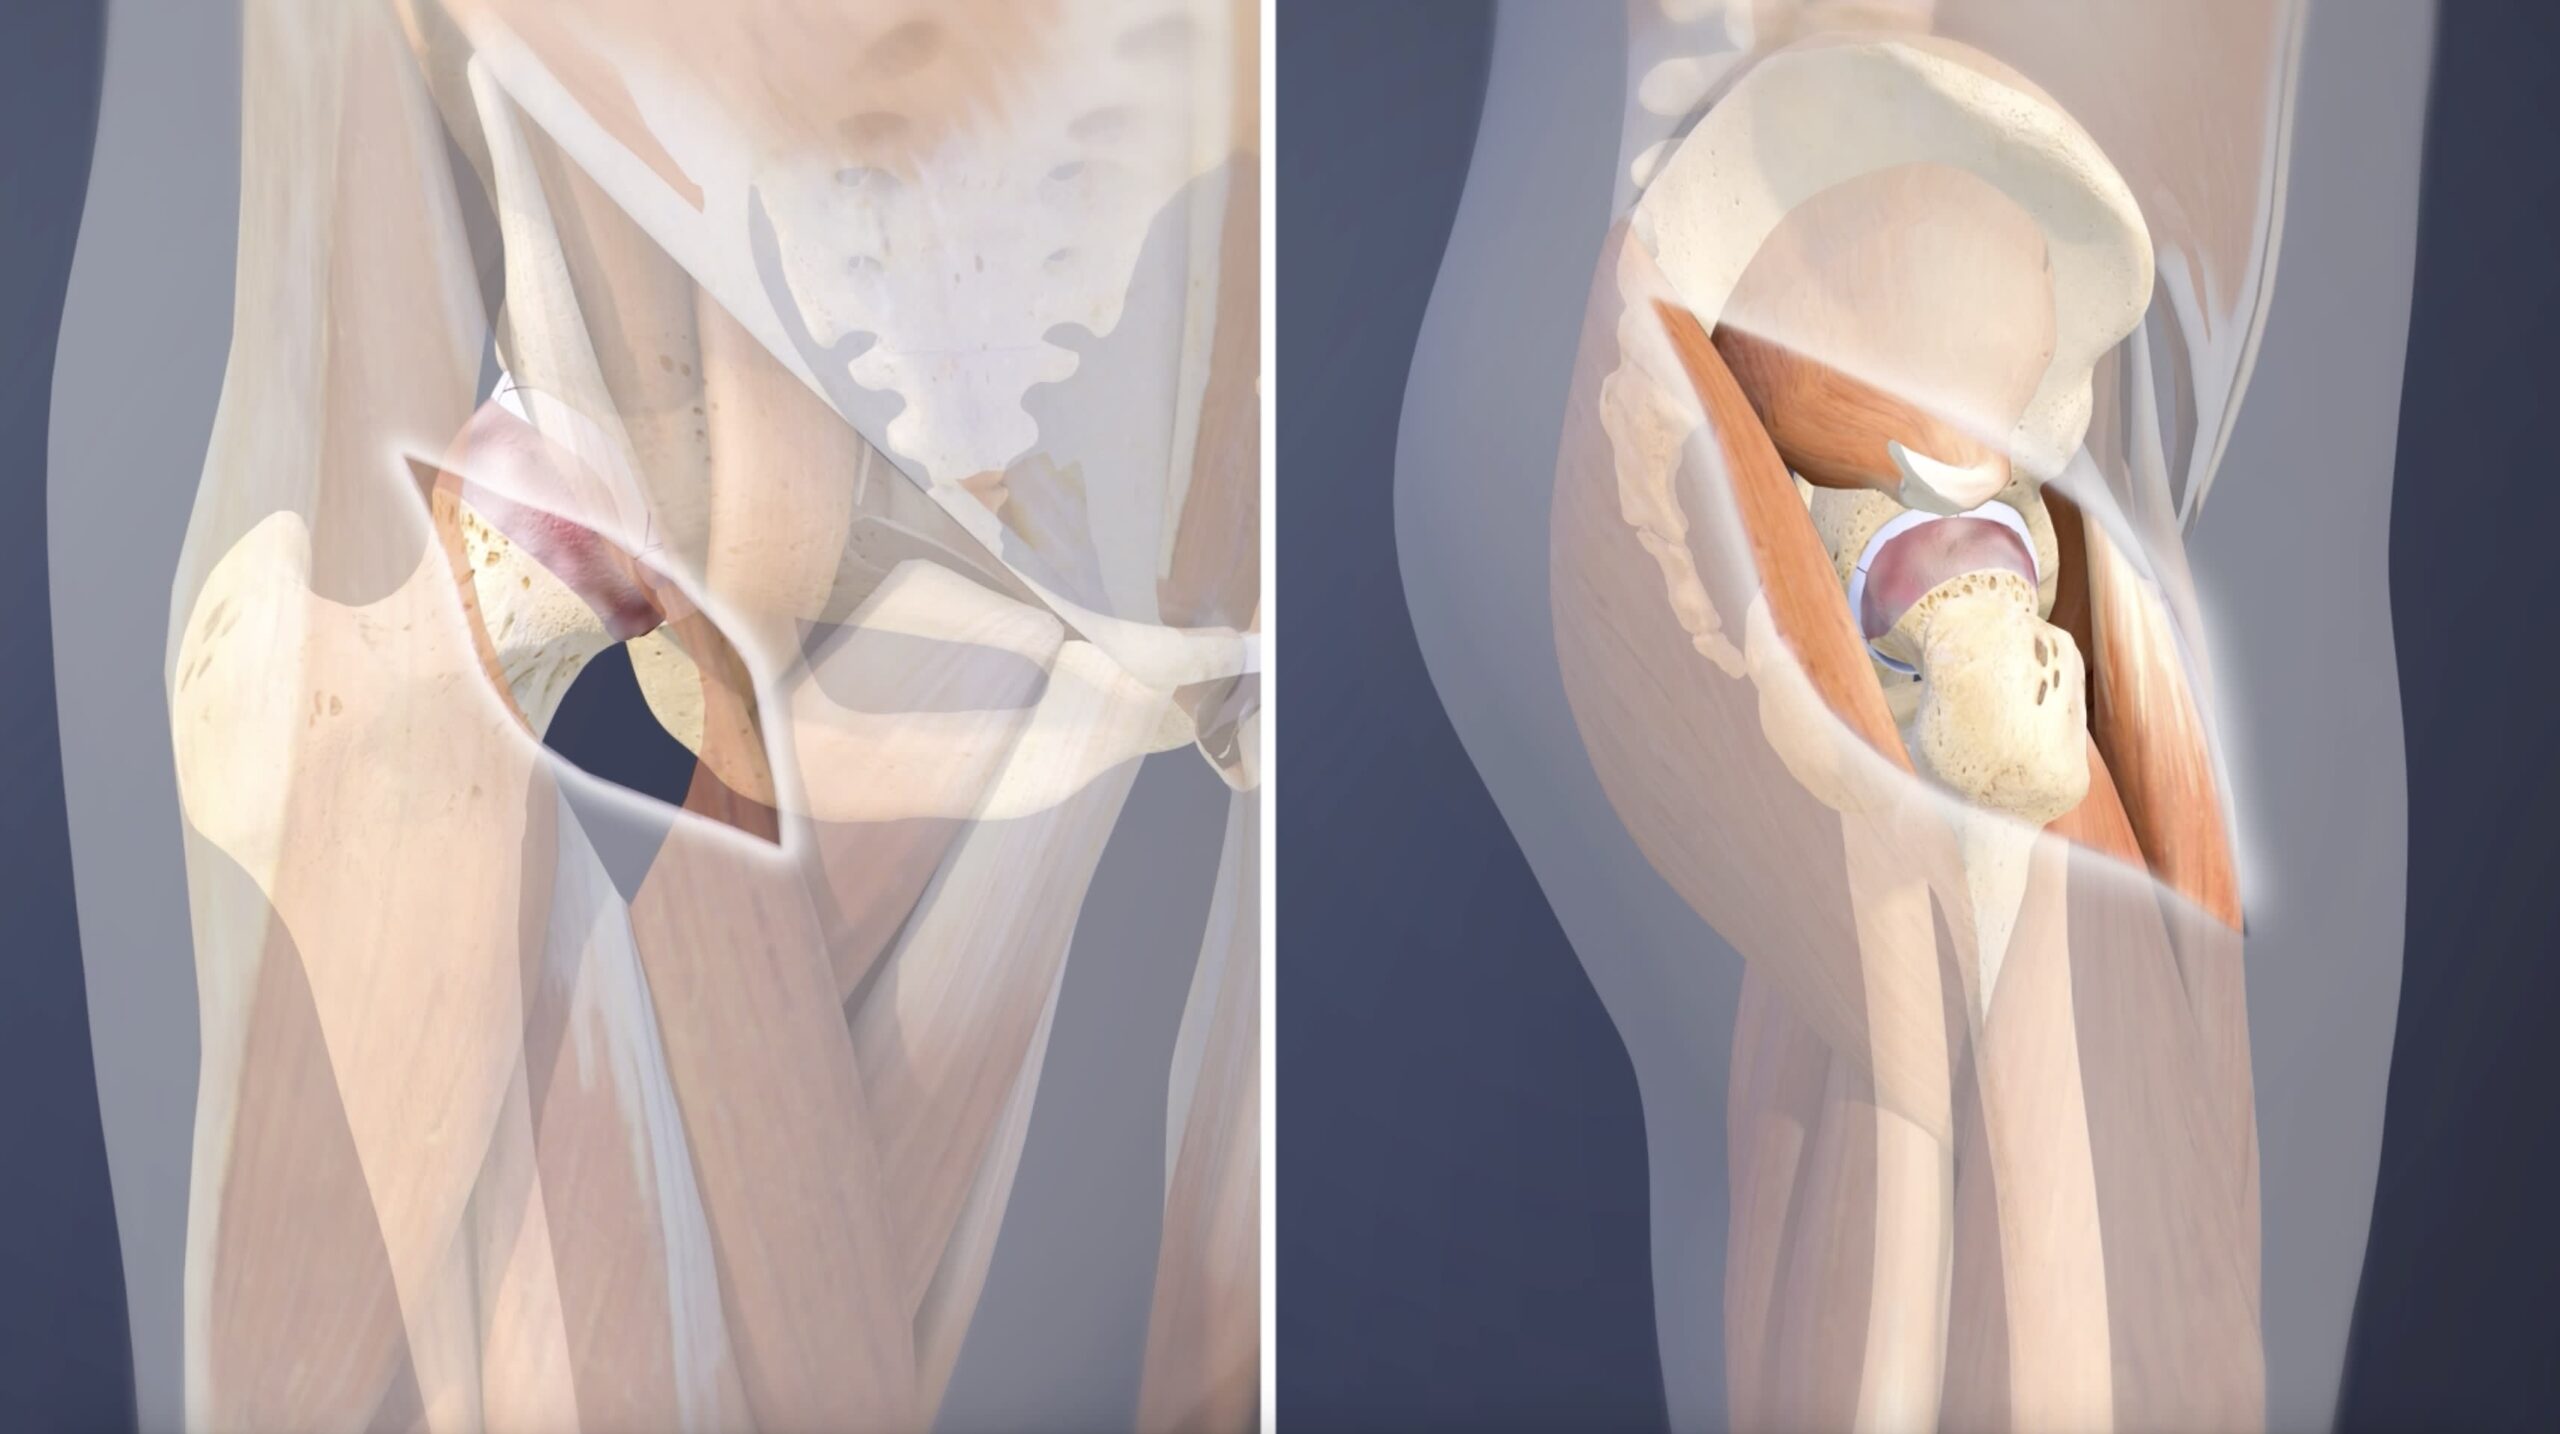

Minimally Invasive Joint Replacement In Nagpur – Dr. Abhishek Bhalotia …

Introduction: Why Robotic Hip Replacement in Korea Is a Global …

Introduction: Why Robotic Knee Replacement in Korea Is Changing Orthopedic …